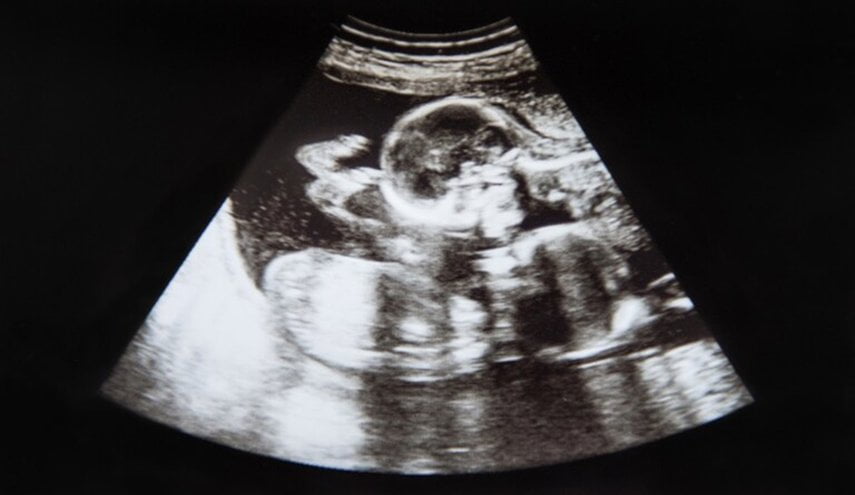

اختفى جنين طفلة في رحم أمها، لكنها تركت لشقيقها التوأم، علامة تشبه صورتها الخاصة على جسمه.

ولدى بايلون غيفنز علامة مميزة على ركبته على شكل حبة “الكاجو”، على غرار شكل شقيقته التوأم، عندما تم فحصهما في الرحم في الأسبوع العاشر من الحمل.

ولم يستطع الأطباء العثور على نبضات قلبها بعد 11 أسبوعا من الحمل، ما أثار مخاوف من نموها بوتيرة أبطأ من شقيقها بايلون.

ووصف الأطباء هذه الحالة باسم “متلازمة التوأم المتلاشي”، وهي ظاهرة يختفي فيها جنين أو أكثر في حالة الحمل بتوائم، ويحدث للجنين إجهاض تلقائي، لكنه يمتص بواسطة الجنين الآخر أو الأم أو المشيمة.